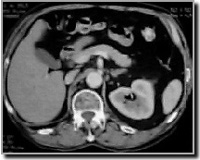

CT-scan van het abdomen of het kleine bekken

CT scan van het abdomen

Een CT-scan van het abdomen of het kleine bekken worddt genomen om eventuele problemen ter hoogte van de darmen, lever, nieren, milt, enz... te beoordelen.

Ook hier is het van groot belang dat de patiëtn tijdens het onderzoek niet beweegt. Er zal een aantal keren gevraagd worden om de adem op houden. Dit is eveneens belangrijk om een goede continuiteit van de beelden te garanderen.

Behalve wanneer het onderzoek wordt gedaan om een beeld te krijgen van de bloedvaten en de beenderstructuren, wordt in principe altijd contrast gegeven om te drinken. Intraveneuse contrast wordt toegediend behalve bij beenderonderzoeken.

Hier is dan een goede voorbereiding nodig.

De dag voor het onderzoek wordt er een reinigingslavement gegeven of een oraal laxeermiddel.

De dag van het onderzoek moet de patiënt een liter contrastmiddel drinken over een uur tijd. Dit om de darmen zo goed mogelijk te vullen. Op die manier kan een duidelijk beeld gevormd worden van de darmen. Ook is een lavement met contrast soms noodzakelijk. Dit om de laatste delen van de darm te vullen.

(Nota: in sommige centra geeft men in plaats van een lavement reeds de dag voordien een fles verdund contrast. Dit geeft echter een minder duidelijk beeld van de laatste darmlissen.)